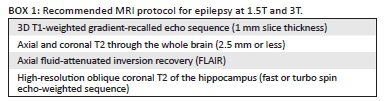

- FCD Type III - Type IIIA: includes FCDs with an associated lesion such as hippocampal sclerosis (Figure 3). Type IIIB: an epilepsy-associated tumour. Type IIIC: vascular malformation. Type IIID: other lesions.

Features of FCD on MRI include cortical thickening (which should be confirmed in at least two planes and on two different imaging sequences), blurring of the gray and white matter junction, T2 and FLAIR hyperintensity in the cortex and adjacent subcortical white matter, T1 shortening in the cortex and abnormal sulcal/ gyral pattern. MRI is able to show abnormalities in the majority of Type II dysplasias but only in some of the Type I cortical dysplasias although, in practice, it may be possible to distinguish between Type I and Type II.7 The typical appearance of FCD Type IIB (with balloon cells) is a band of hyperintensity on T2-weighted and FLAIR images extending from the gray and white matter interface to the surface of the ventricles (Figure 2). To visualise this often subtle finding, multiplanar thin-section images should be performed. At 3T, volumetric FLAIR with multiplanar reformats is an excellent sequence to look for the white matter hyperintensity characteristic of Type II FCDs.